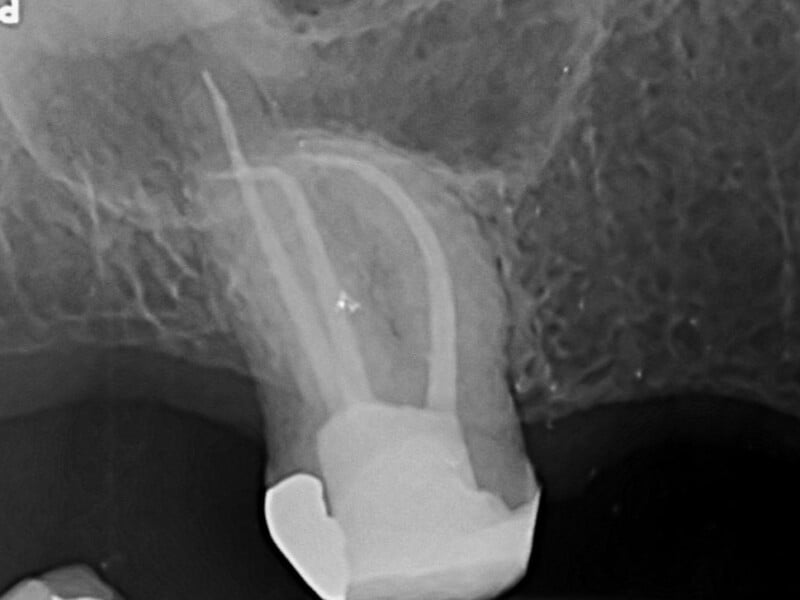

Tooth / teeth to be evaluated / treated